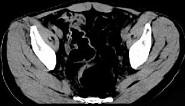

问题 女,51岁,腹胀、腹痛、进行性消瘦,影像检查如下图,最佳诊断是 ( )

选项 A.乙状结肠Crohn病 B.乙状结肠结核 C.乙状结肠癌 D.乙状结肠淋巴瘤 E.乙状结肠息肉

答案 C